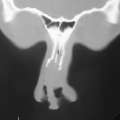

Rhinoplasty

Rhinoplasty, or surgery to reshape the nose, is one of the most common of all plastic surgery procedures. Rhinoplasty can reduce or increase the size of your nose, change the shape of the tip or the bridge, narrow the span of the nostrils, or change the angle between your nose and your upper lip. It may also correct a birth defect or injury, or help relieve some breathing problems.

Rhinoplasty usually takes an hour or three, though complicated procedures may take longer. During surgery the skin of the nose is separated from its supporting framework of bone and cartilage, which is then sculpted to the desired shape. The nature of the sculpting will depend on your problem and your surgeon's preferred technique. Finally, the skin is rewrapped over the new framework.